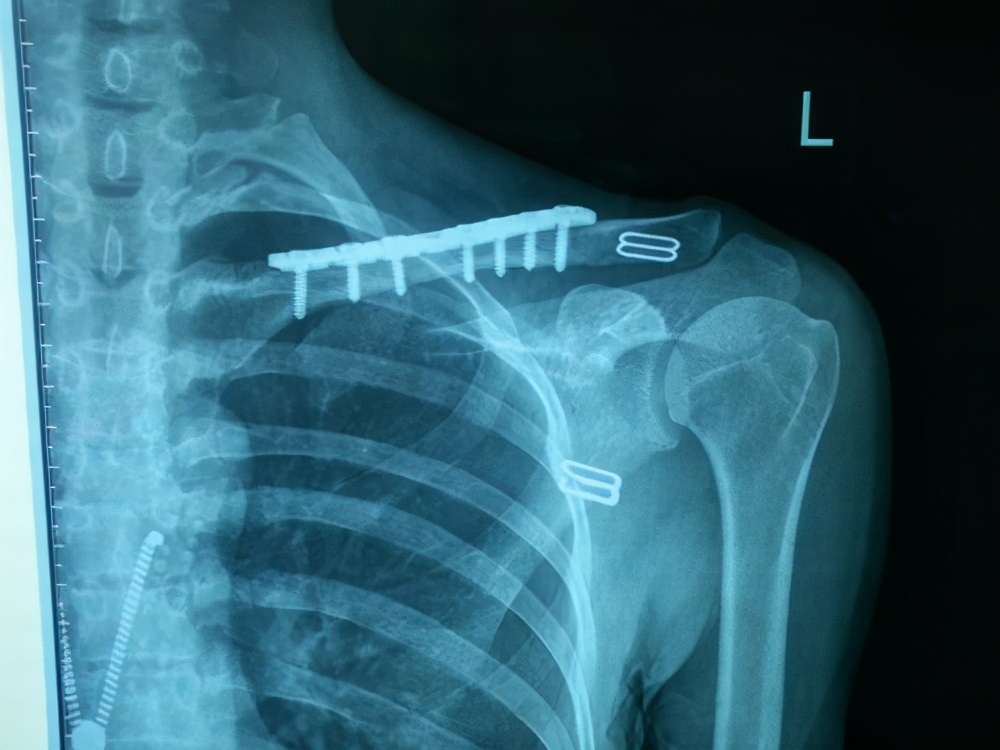

3、影响到功能了:我骨折愈合了,但是由于钢板的原因导致我一些功能的丧失,比如 锁骨钩钢板,这是带钩的钢板,不同于那些直钢板,有的人 会在抬胳膊的时候感觉钢板在撞击我的肩膀,这个时候那就要尽量取掉了;建议6-8个月来取,足踝关节部位的钢板,如果踝关节的功能受到影响,建议取出。

锁骨钩钢板

锁骨直板